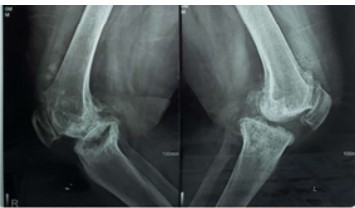

Autogenous structural bone graft reconstruction of uncontained significant medial proximal tibial bone defects in primary total knee arthroplasty

Anwar Abdulqader Mughalles, , Abdulrakib Saleh Almirah, Abdulkareem Esmail Alsabri, Marwan Mohammed Farhan, Ghamdan Gamal Alkholidy (Author)

489 - 496